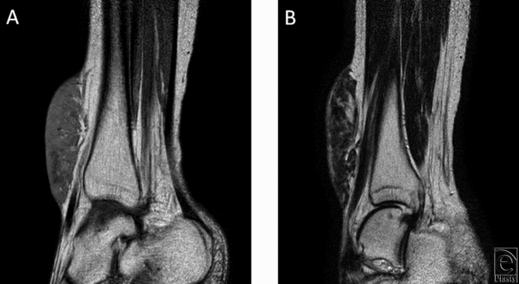

A 47-year-old Asian woman presented with a long-standing history of a blue-gray dome-shaped soft mass sized 10 × 6 × 2 cm on the anterior aspect of her right lower leg (Fig 1). She and her mother stated that the mass has been observed since birth and had enlarged slowly with her growth. Inguinal lymph node swelling was not palpitated. Magnetic resonance imaging showed T1 hypointensity, T2 hyperintensity, and an irregular border on the deep side (Fig 2). Normal vessels and fat were present in the mass, but tumor invasion was not observed. The study was approved by the ethics committee of our hospital (Kyoto Prefectural University of Medicine).

| Figure 2. Magnetic resonance imaging findings. (a) T1 hypointensity and (b) T2 hyperintensity, irregular border on the deep side, and normal vessels and fat running through the mass. |